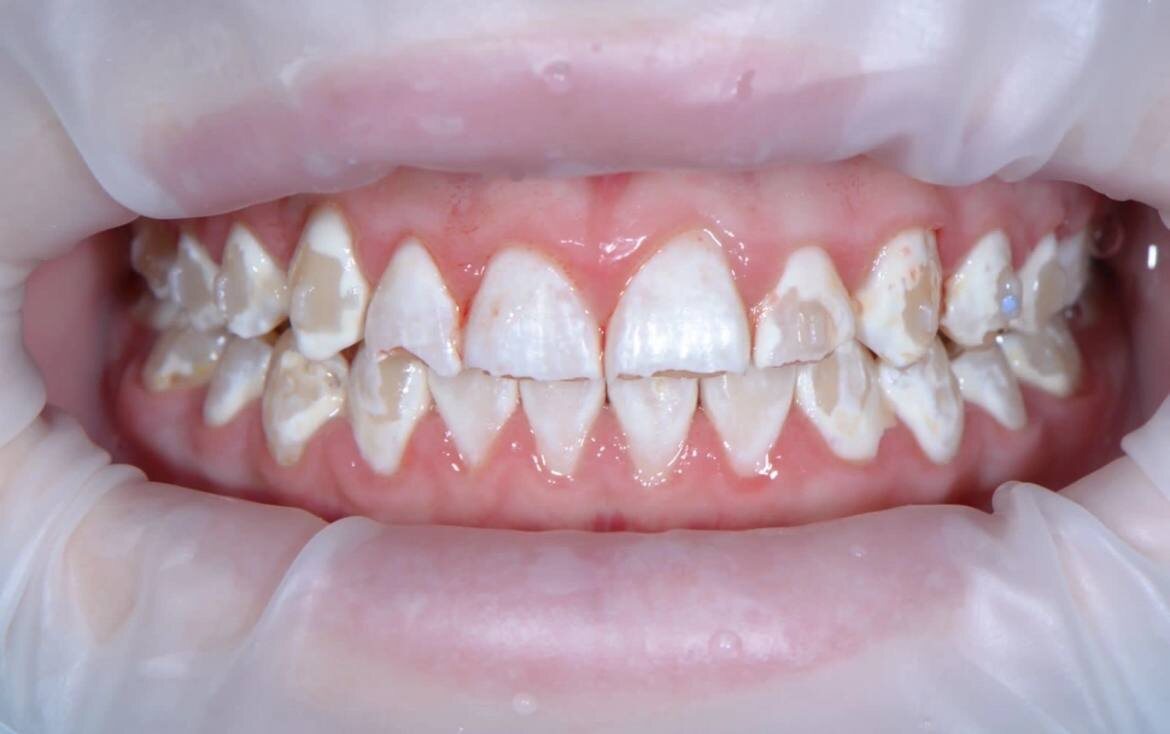

Эрозии на вестибулярной поверхности - вредные привычки сосать что-то кислое.

Эрозии на всех поверхностях - питиё и поедание кислоты в неконтролируемых дозах + неправильное поведение после.

Эрозии на фронтальной поверхности зубов

Так же хочу напомнить про типичный налет, характерный для кислотного воздействия на зубы - коричневатый такой, даже не налёт, а пигмент. Располагается на жевательной поверхности, в фиссурах. Там, где в норме мы его не видим почти никогда.

Типичный для эрозий налёт

Камней - нет.